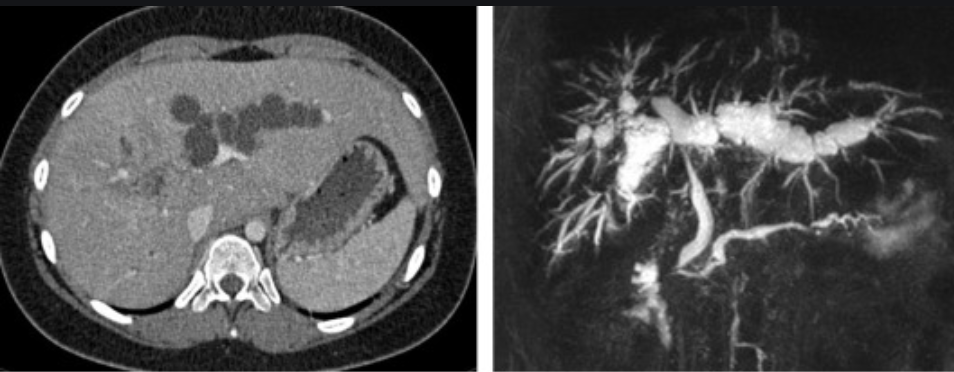

Caroli syndrome.

Dilated ducts Dx

Dx?

Biliary MR

DDx cystic hepatic lesion

Choledochal cysts